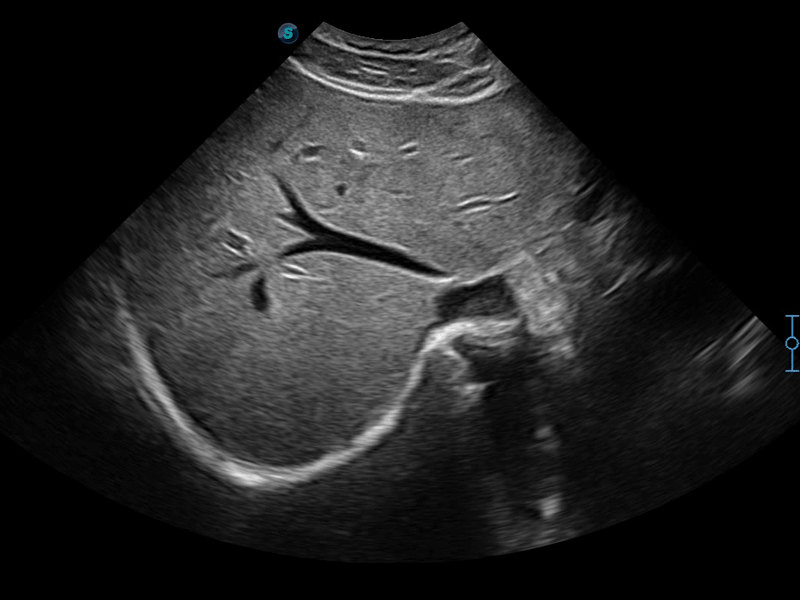

μ-Scan+新一代微米成像技术

新一代微米成像技术大大提高了器官和病变的可见性。高清对比度分辨率将抑制斑点噪声,同时保持真实的组织结构。

扩展成像技术

凸阵、线阵和相控阵探头进行实时扫描时,开启扩展成像模式,可以扩展超声图像视野,以便更完整地查看大的病灶或组织器官的解剖结构。